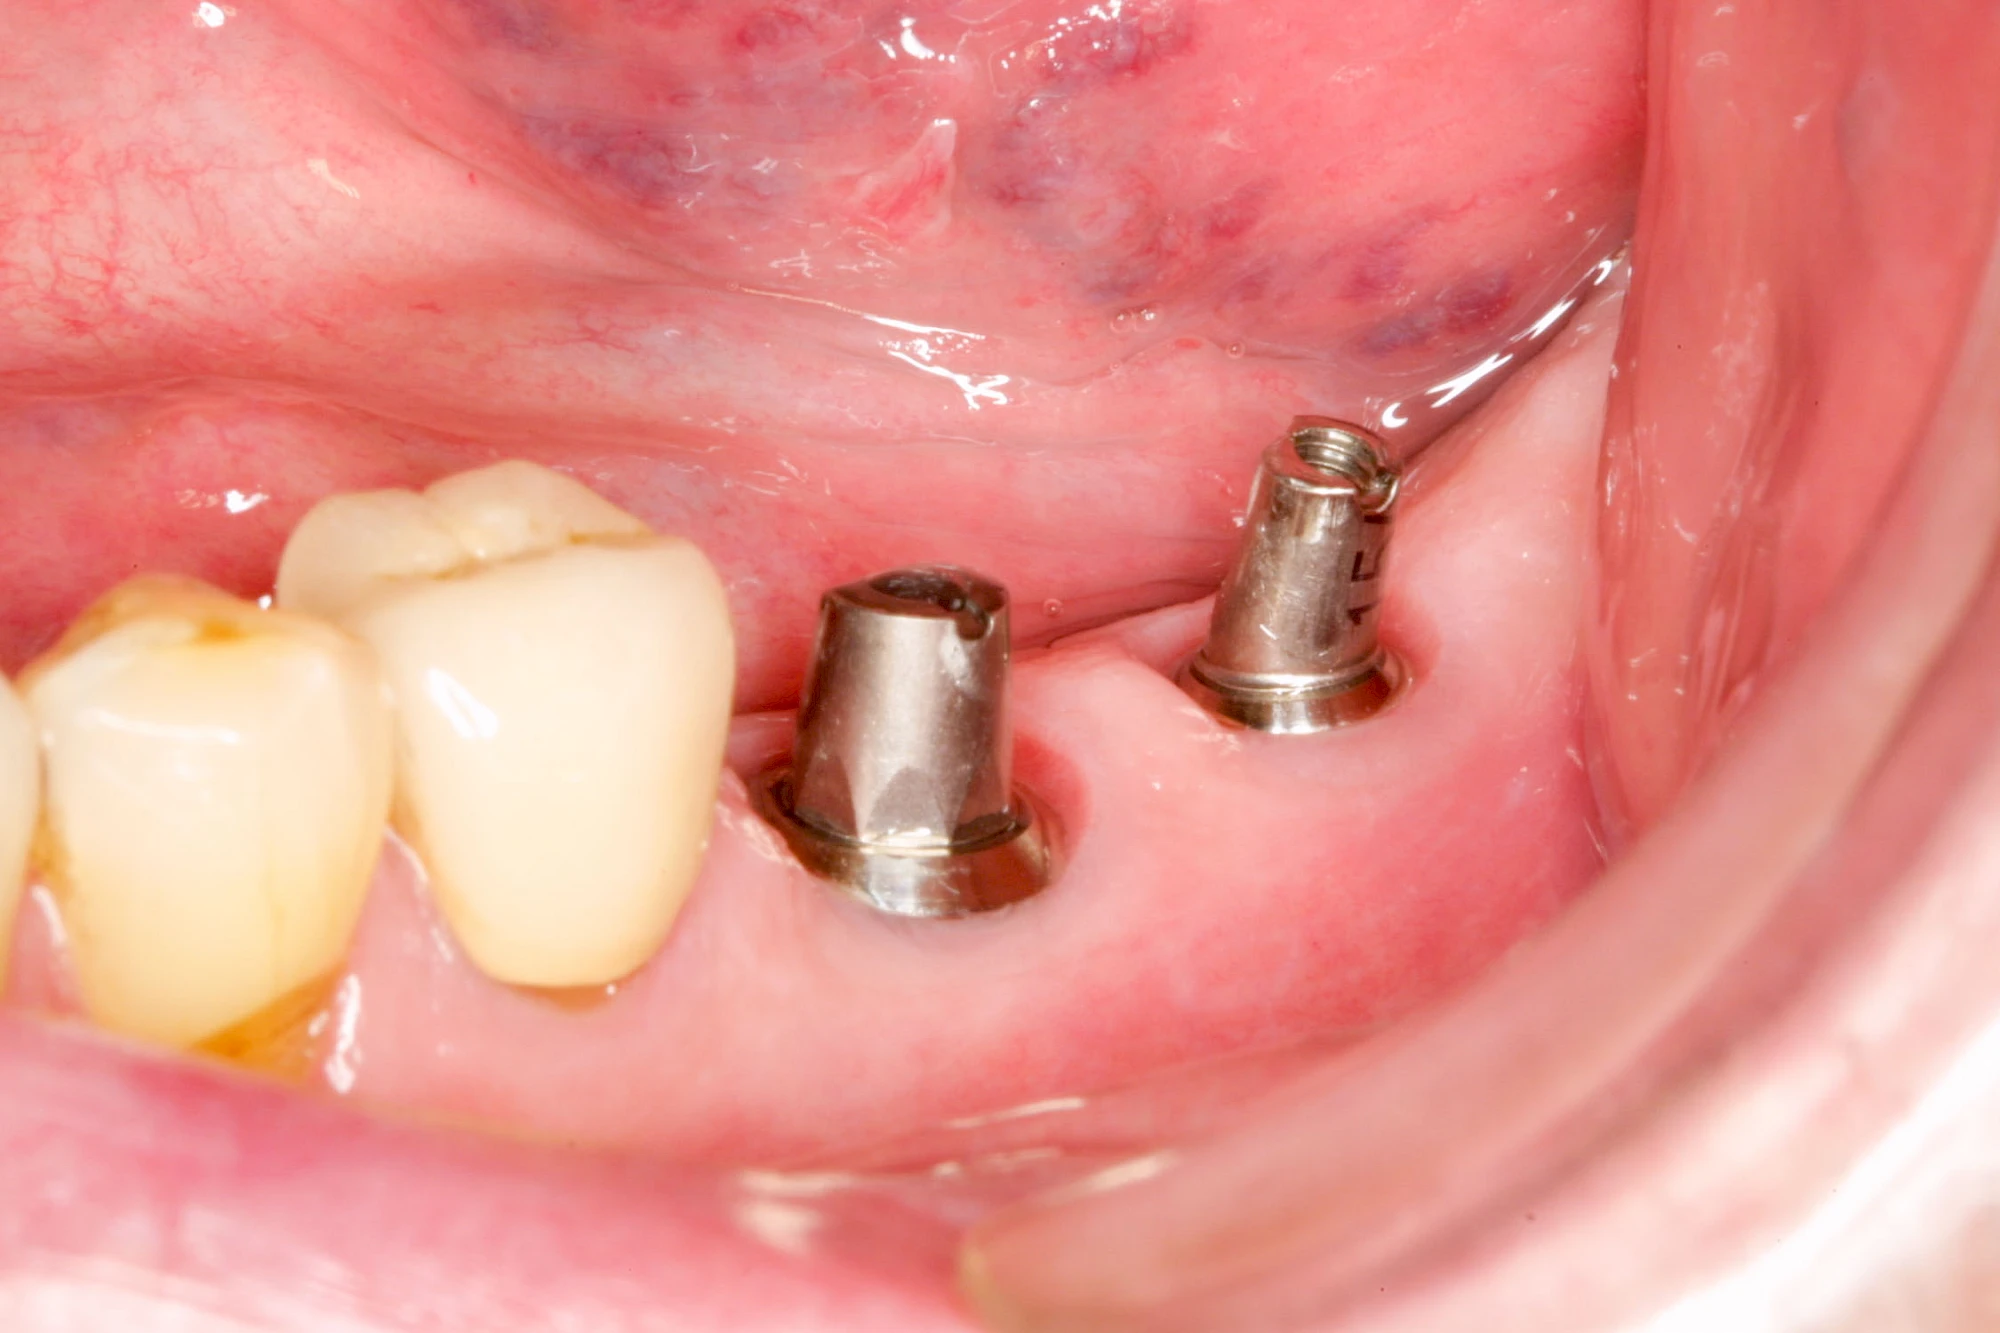

Implantate: Bestandteile

Implantate sind künstliche Zahnwurzeln. Nach einer gewissen Einheilzeit im Knochen (meist 3-6 Monate) erfolgt über einen separaten Aufbau (Abutment) die Befestigung einer Krone bzw. Brücke oder Zahnprothese.

In seltenen Fällen sind Implantate samt Aufbau aus einem Stück gefertigt. Auch gibt es Situationen, die ein Früh- oder sogar eine Sofortbelastung erlauben – dann kann die Einheilzeit der Implantate in den Knochen verkürzt oder sogar gänzlich darauf verzichtet werden.